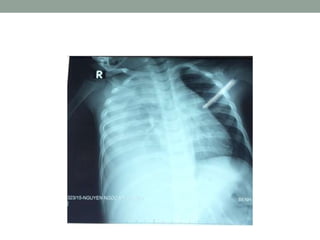

Xquang:

• Có thể thấy hình ảnh xẹp phổi trong tắc hoàn toàn.

• Nếu tắc không hoàn toàn, không khí vào nhưng không ra

được, nên sẽ có tình trạng ứ khí.

Xẹp toàn bộ Vừa tràn khí vừa xẹp

TẮC NGHẼN HÔHẤP DƢỚI Xquang: • Có thể thấy hình ảnh xẹp phổi trong tắc hoàn toàn. • Nếu tắc không hoàn toàn, không khí vào nhưng không ra được, nên sẽ có tình trạng ứ khí.

Xẹp toàn bộVừa tràn khí vừa xẹp